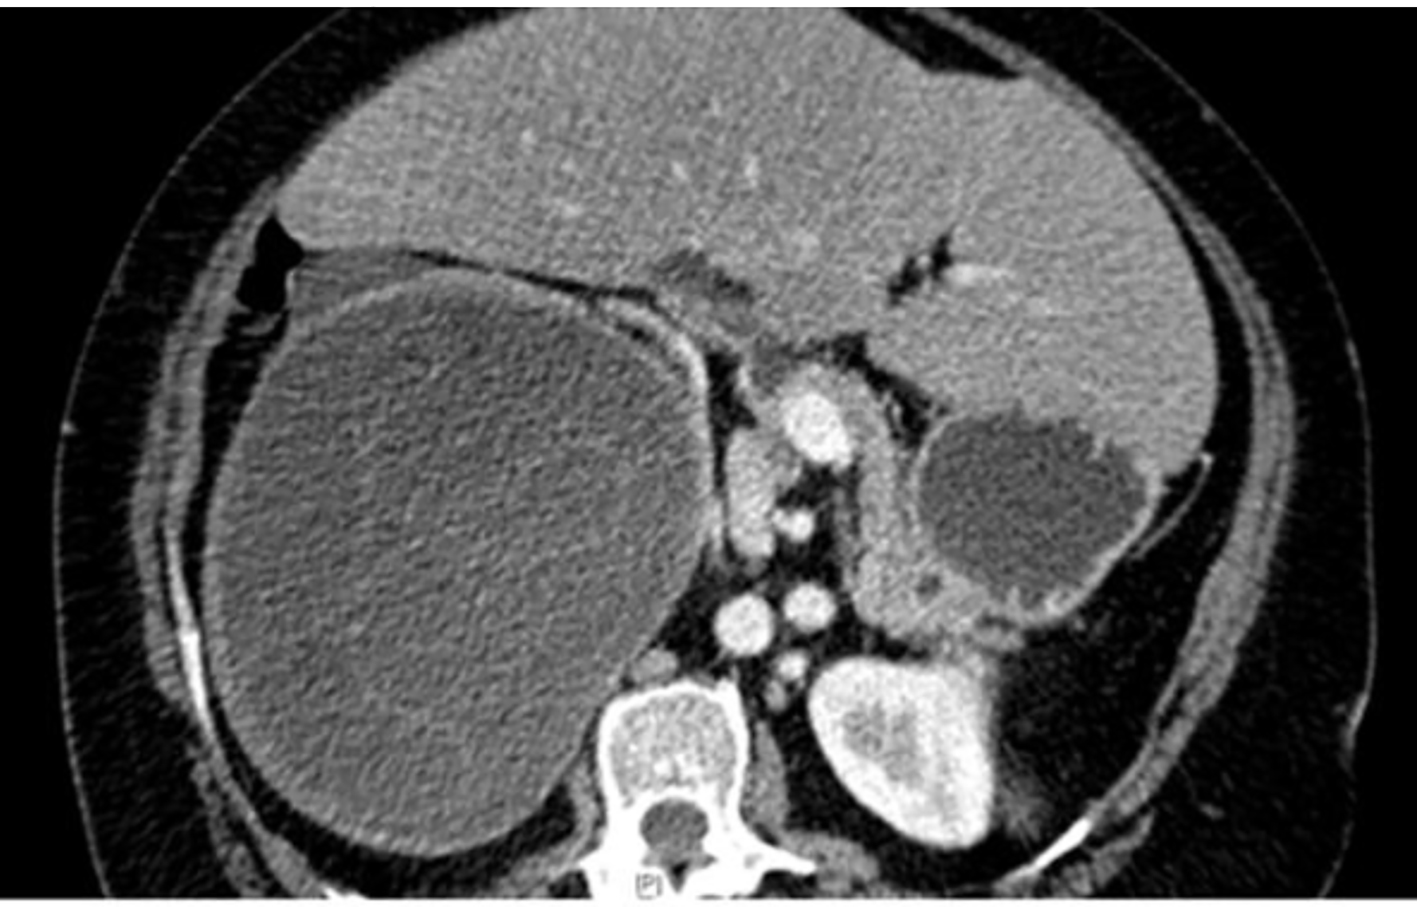

A 65-year-old woman with DM and hypertension was admitted to hospital with 8 years history of right lumbar pain. She used to live in the desert with strong history of contact with animals including dogs. She denied any urinary or other systemic symptoms. General examination was normal. Abdominal examination showed a 7 × 6 cm paraumbilical hernia. US abdomen showed a complex cystic structure measuring 20 × 9.4 cm occupying the right renal region that revealed multiple septations, coiled membranes and internal debris. Several internal small cysts are seen, features of which were consistent with hydatid cyst (Fig. 1, 2). Similarly, MRI disclosed a huge cystic lesion involving the upper and mid pole of the right kidney producing anterior displacement of the liver and pancreas with a thin T2 hypointense wall. There is a long smoothly outlined linear structure within the cyst, which includes multiple tiny cysts, likely representing an infolded ruptured wall of a hydatid cyst (Fig. 3). CT scan of the abdomen, chest and pelvis confirmed a giant hydatid cyst in the right kidney with no evidence of other cysts in the liver or the lungs (Fig. 4). The eosinophil count was normal both before and after surgery. Serum creatine remained normal despite a right kidney contributing only 5% of the renal function on DMSA scan. Urine and aspirate of cyst fluid was repeatedly negative for hydaturia. IHA serology for hydatid was also negative.

![]() Click for large image | Figure 4. CT scan abdomen - huge hydatid cyst in the right kidney. |